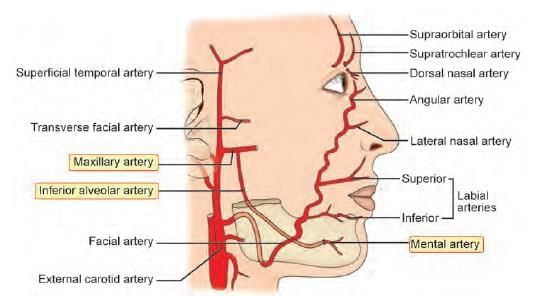

Which of the following is NOT a branch of facial artery? (INI-CET May 2022)

External carotid artery supplies nasal septum by all of the following branches, except: (AIIMS May 2019)